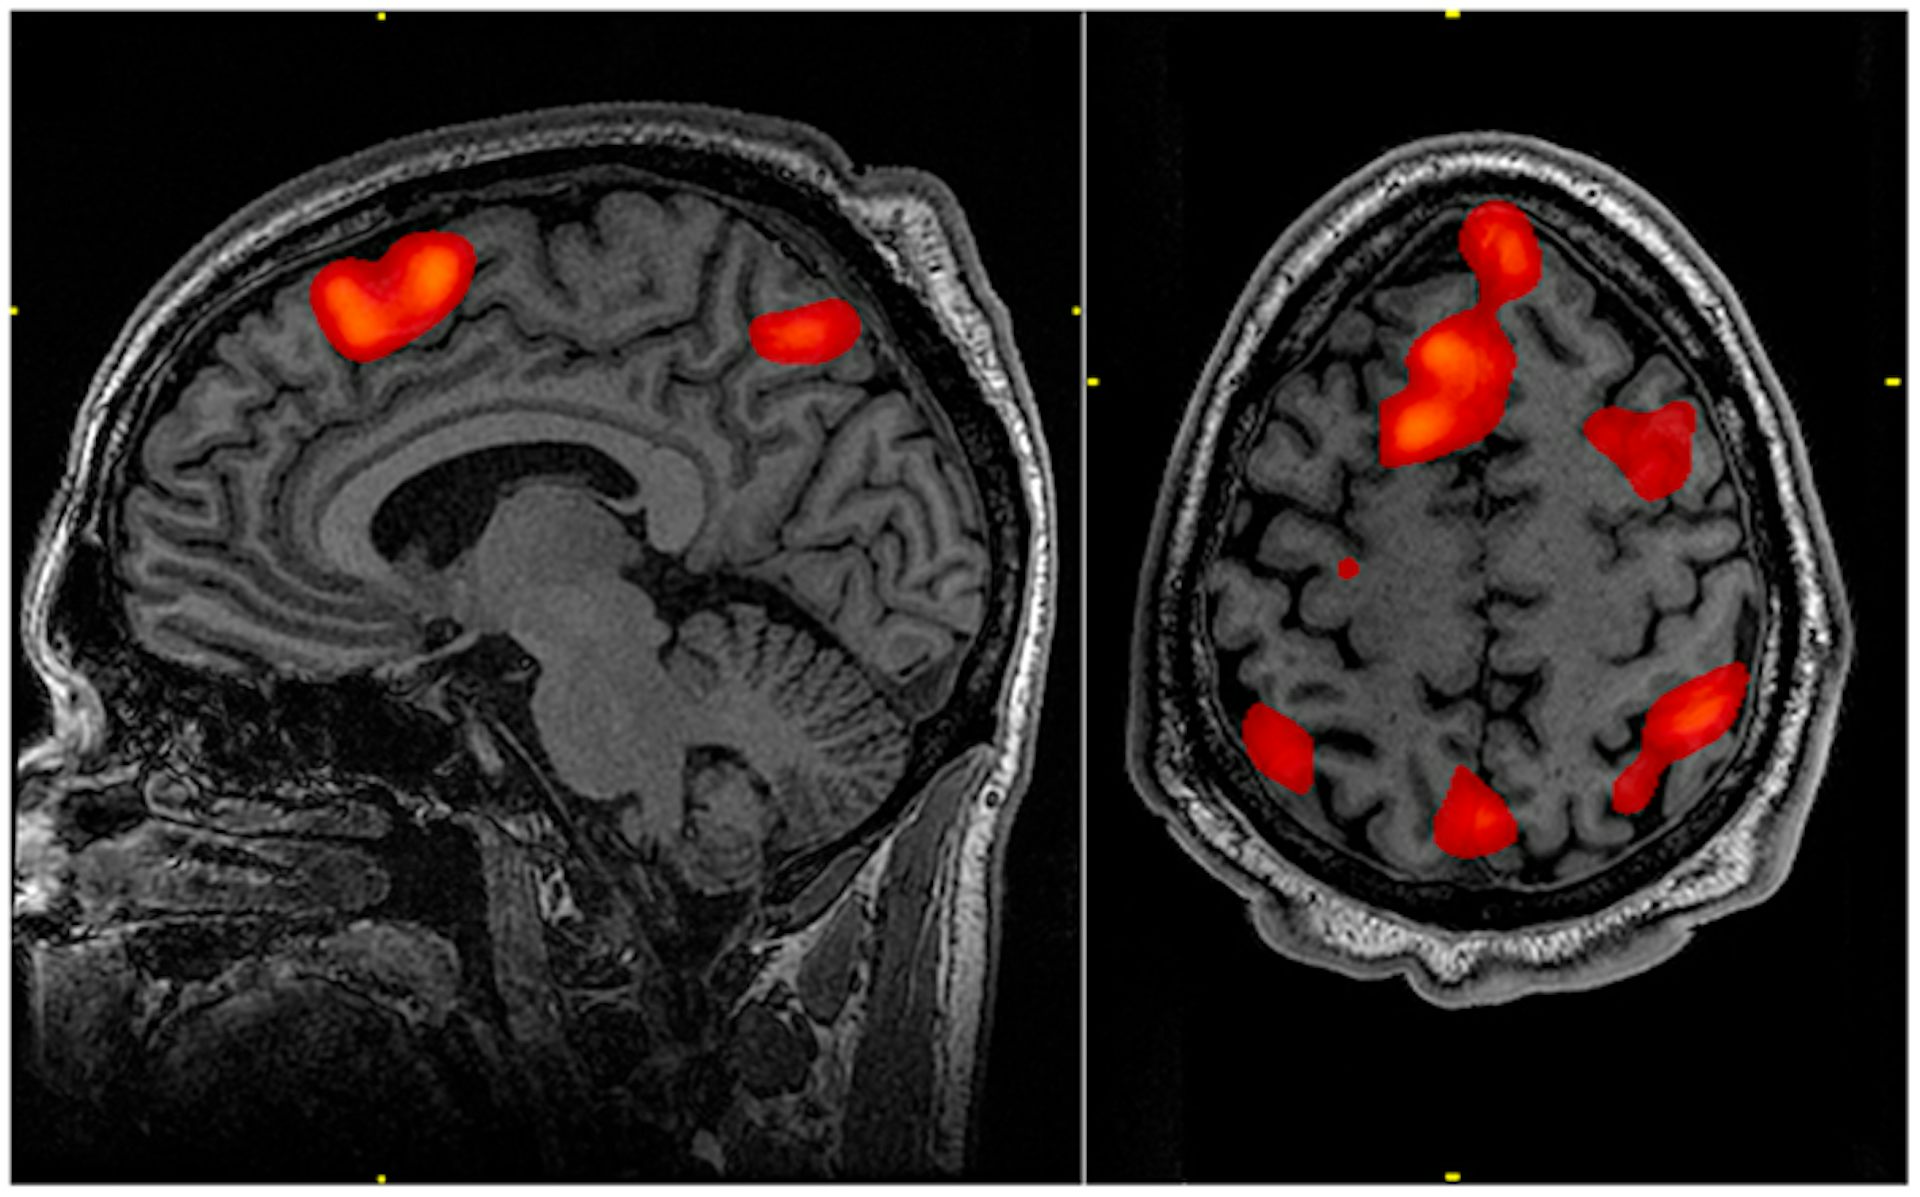

Functional magnetic resonance imaging is used for this operation. This is the name of a type of magnetic resonance imaging, which is performed to measure hemodynamic reactions (changes in blood flow) caused by neuronal activity in the brain or spinal cord. The method is based on the fact that cerebral blood flow and neuronal activity are interconnected.

When an area of the brain is active, blood flow to that area also increases.

The scientists who conducted the experiment scanned the brain activity of all participants using functional magnetic resonance imaging with additional magnetic resonance imaging data. This is already a way to obtain tomographic medical images for the study of internal organs and tissues using the phenomenon of nuclear magnetic resonance. It is based on measuring the electromagnetic response of atomic nuclei, most often the nuclei of hydrogen atoms, namely, on their excitation by a certain combination of electromagnetic waves in a constant magnetic field of high intensity.

The computer system, after analyzing the tomography data, showed that the "criminals" who violated, realizing the presence of contraband, activated other parts of the brain than those volunteers who walked through the checkpoint, not knowing if everything was in order with things in their portfolio.

In the first case, the analysis showed the activity of the middle prefrontal cortex of the brain. This, according to modern scientists, is the area that is responsible for the self-awareness of a person. She is also responsible for the behavior of a person who expects a reward or punishment. Also in this case, the temporo-parietal region became active, starting to work when a person utters a deliberate lie.

Those volunteers who were not aware of what was in the briefcase activated the occipital cortex, which is mainly responsible for processing visual information.